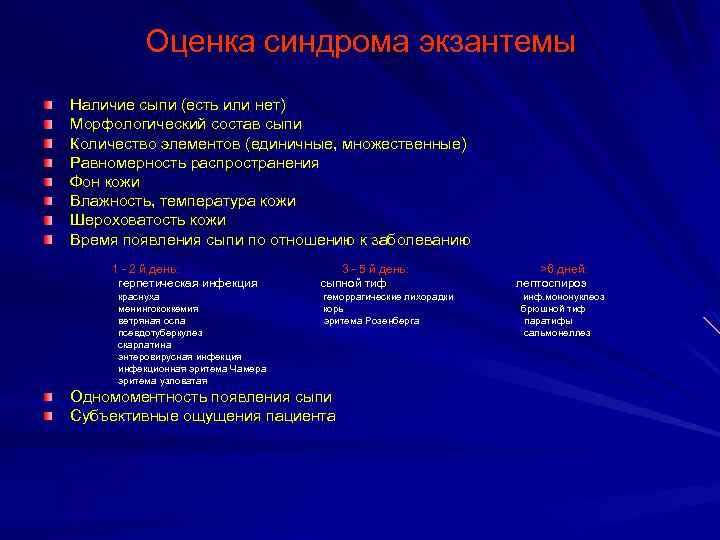

Дифференциальная диагностика заболеваний плевры